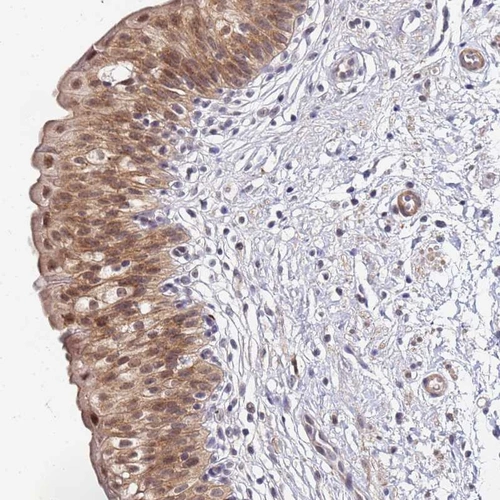

Immunohistochemical staining of human urinary bladder shows moderate cytoplasmic/nuclear positivity in urothelial cells with additional membranous positivity.